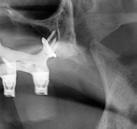

Exploración radiológica

Mediante CBCT constatamos atrofias óseas severas y disminución de soporte óseo periodontal en relación con las piezas dentales.

A tenor del estado oral proponemos múltiples opciones terapéuticas, consensuando entre paciente y facultativos una rehabilitación implantoprotésica fija superior e inferior. Debido a la lejanía de la residencia de la paciente, y motivados por las necesidades estéticas que esta exige, consideramos realizar una carga inmediata impresa con resina definitiva el mismo día de la cirugía. Tras el escaneado intraoral con el escáner Dexis IS3700 (Figuras 7 y 8) y realización de CBCT, subimos los ficheros a la plataforma Bego Guide,

procediendo a realizar una solicitud de encargo a través de un formulario. Antes de 72 horas recibimos una propuesta terapéutica. En ella se facilitan vistas 3D detalladas, así como valoraciones y consideraciones a tener en cuenta durante el fresado y la inserción de los implantes (Figuras 9 a 19). Decidimos realizar extracción de todas las piezas remanentes, dada su nula viabilidad a corto-medio plazo y en Bego (a través del portal) proponen mantener 3 piezas (las más viables técnicamente) en cada arcada para proporcionar el anclaje óptimo de la

Uno de los aspectos que nos convenció para utilizar un sistema guiado fue la baja tasa desviación que presentan los implantes. Si bien la cirugía a mano alzada es completamente válida, no estamos exentos de que se produzca una desviación de 11.2° ± 5.6° (5), mientras que usando sistemas guiados, dicha desviación se reduce significativamente a un 2.1° ± 1° (6). Otro factor favorable es que contempla la posición tridimensional ideal (7, 8), teniendo en cuenta el espacio de confort, así como una rehabilitación protésicamente guiada a partir de un encerado diagnóstico digital efectuado sobre referencias anatómicas obtenidas de un CBCT y modelos de estudio tridimensionales a través de un escaneado intraoral. Su uso, sin duda, facilita la fase protésica y reduce significativamente los cambios en el plan de tratamiento protésico, teniendo claro, desde el